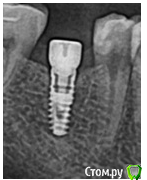

andrey75 Опубликовано 8 сентября, 2015 Автор Поделиться Опубликовано 8 сентября, 2015 Вот и рентген Ссылка на комментарий

Доктор Добрых Дел Опубликовано 8 сентября, 2015 Поделиться Опубликовано 8 сентября, 2015 Вот и рентген[/quote XiVE Ссылка на комментарий

andrey75 Опубликовано 8 сентября, 2015 Автор Поделиться Опубликовано 8 сентября, 2015 Спасибо Всем да это XiVe уже заказал запчасти. Ссылка на комментарий